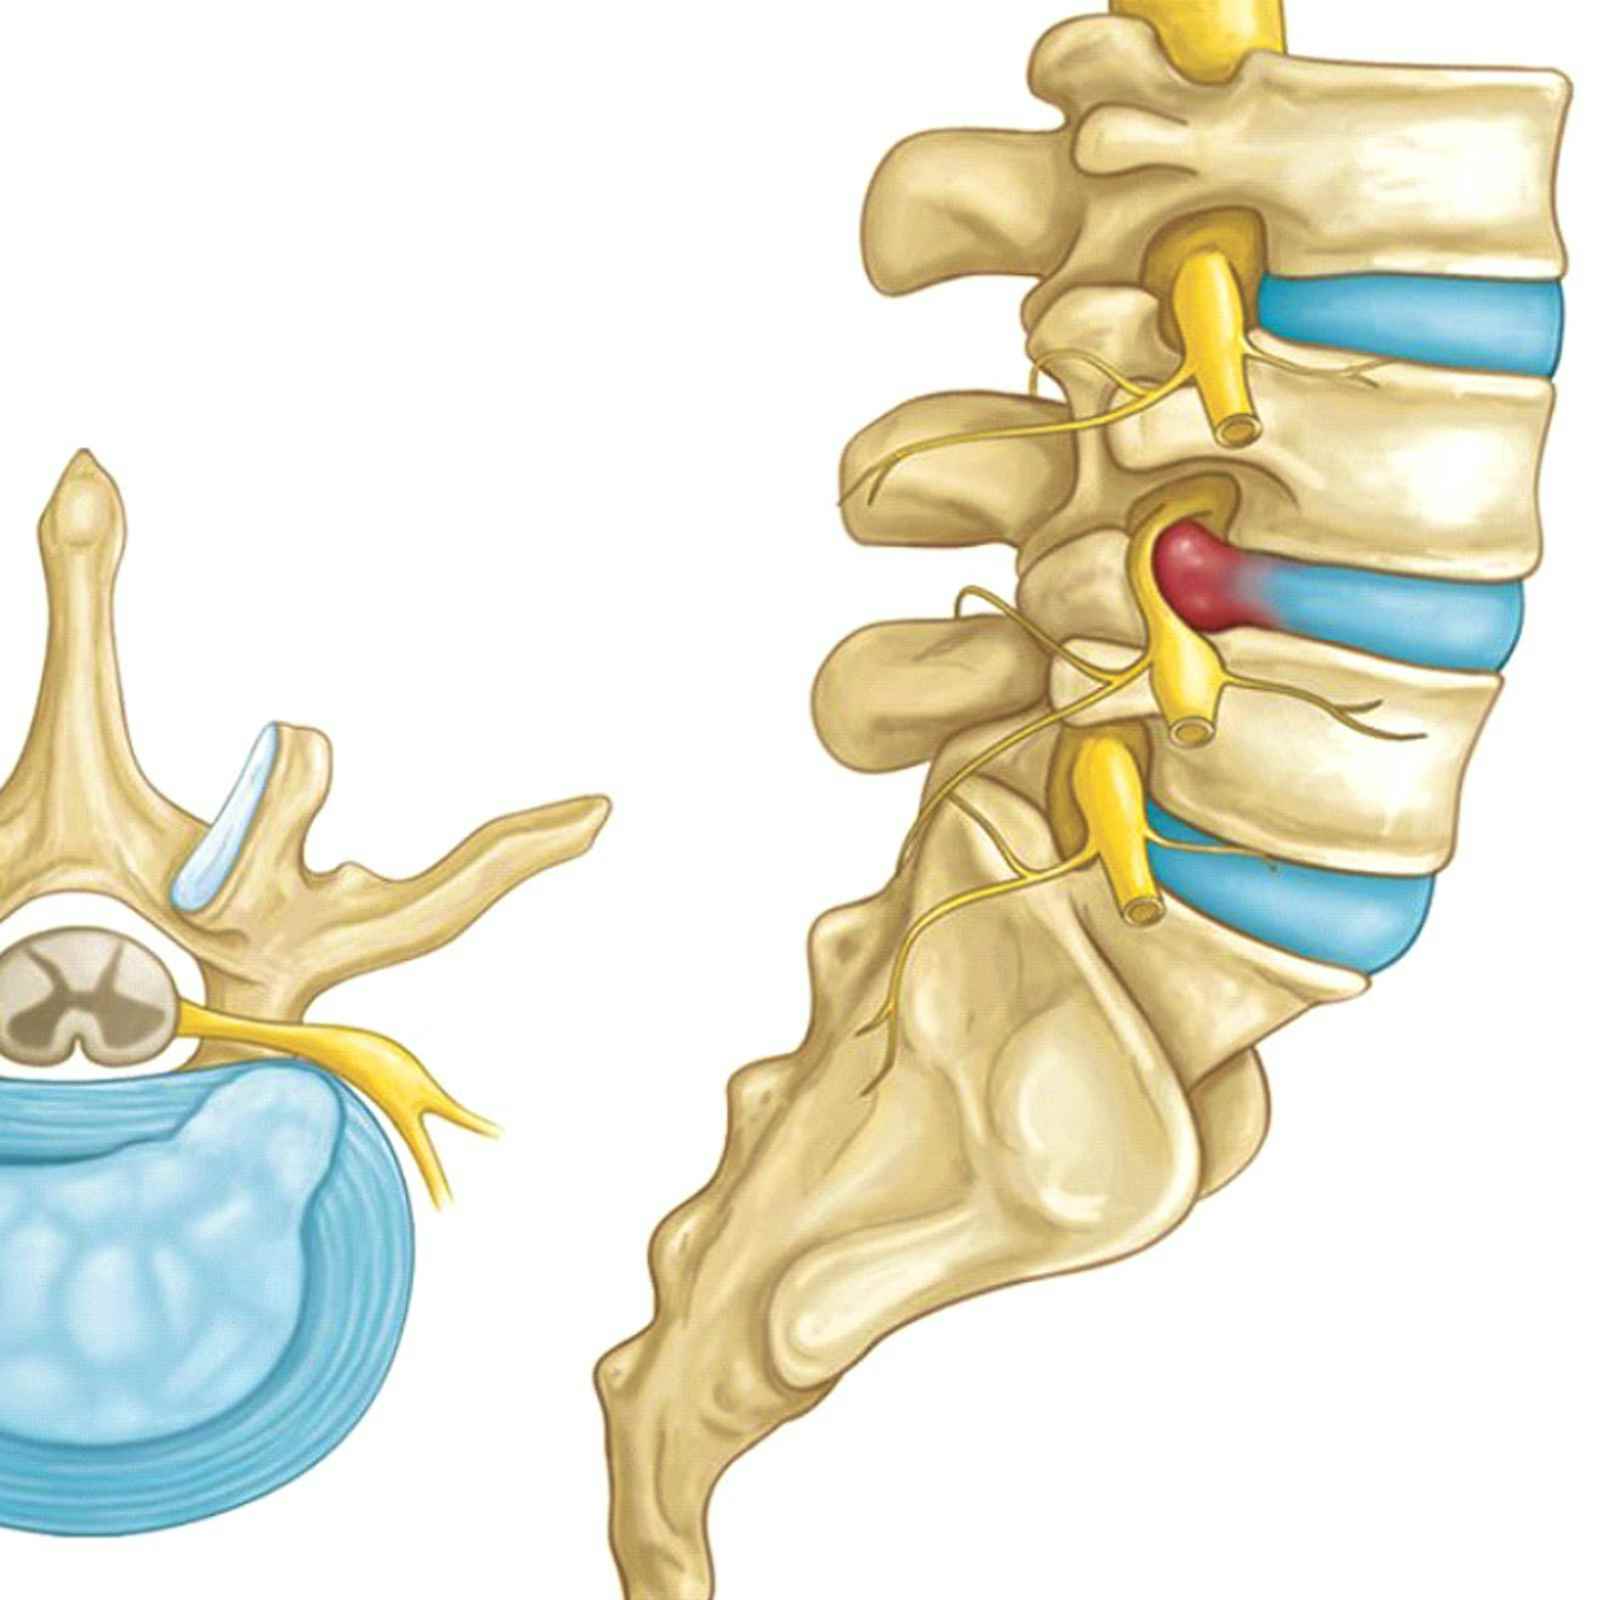

КТ-протрузии дисков: Визуализация и классификация